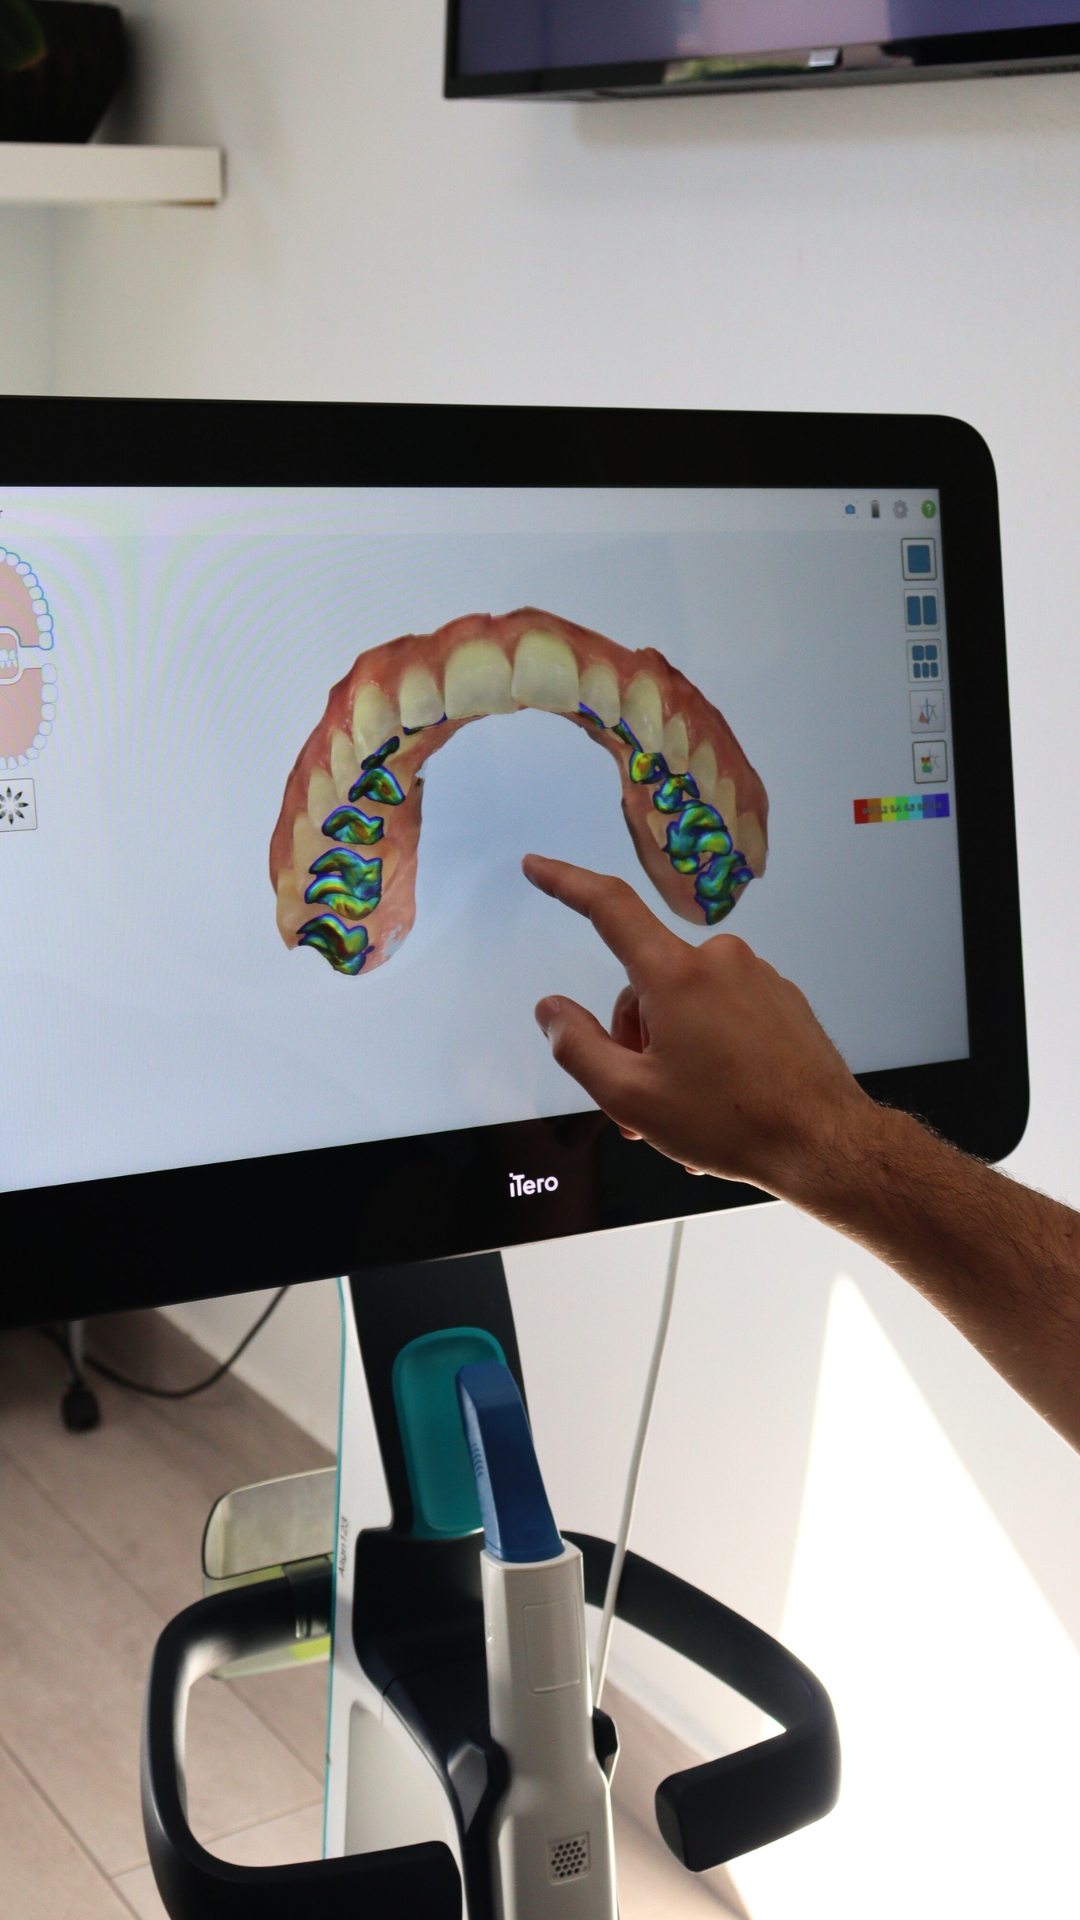

Advanced Digital Planning:

Advanced digital planning is offered, allowing orthodontists to plan each tooth movement with millimetre accuracy. Patients can see a virtual simulation of the expected results, giving them a clear view of the treatment progress.

Advanced Digital Planning:

Advanced digital planning is offered, allowing orthodontists to plan each tooth movement with millimetre accuracy. Patients can see a virtual simulation of the expected results, giving them a clear view of the treatment progress.